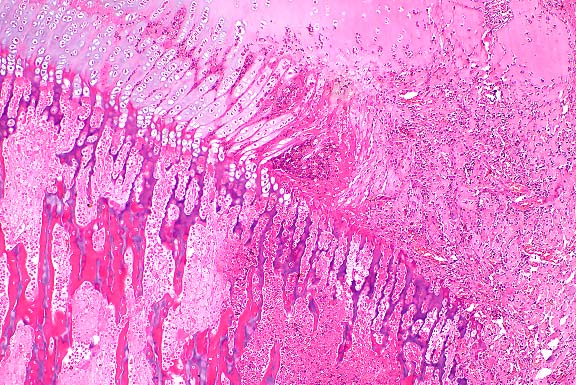

Early lesions appear histologically as multifocal subcutaneous

accumulations of amorphous lightly basophilic material which

is periodic acid-Schiff positive, stains brown with acid orcein

Giemsa, and can be shown by von Kossa stain to contain calcium.

Within the basophilic material, hemorrhage is occasionally seen,

and fractures or fissures are seen commonly, but inflammatory

and fibroplastic responses are negligible. Intermediate lesions

are more likely to have fully mineralized areas within the amorphous

material, which is surrounded by mild to moderate granulomatous

inflammation and fibroplasia. Late lesions are associated with

marked granulomatous inflammation and fibroplasia, with macrophages,

multinucleate giant cells, lymphocytes, and a few plasma cells

and neutrophils. Inflammatory cells are arranged around mineralized

centers in palisading granuloma fashion. Although these centers

are generally acellular, they do incorporate some macrophages,

fibroblasts, and histiocytic giant cells containing phagocytized

mineral. Granulomatous areas are separated by thick connective

tissue septa. Cartilaginous or osseous metaplasia is seen in

56.9% of late lesions. Very old lesions are multilocular, with

thick connective tissue trabeculae, and are characterized by

completely mineralized areas without much active inflammation.

- Case 20-4. Cervical vertebra. Multifocally areas of

endochondral bone partly replaced by granular mineralized debris

are surounded by macrophages, foreign body giant cells, and fibrous

connective tissue.

- AFIP Diagnosis: Cervical vertebral fascia (per contributor):

Granulomas, calcareous (calcinosis circumscripta), with fibrosis

and chondro-osseous metaplasia, German Shepherd Dog, canine.